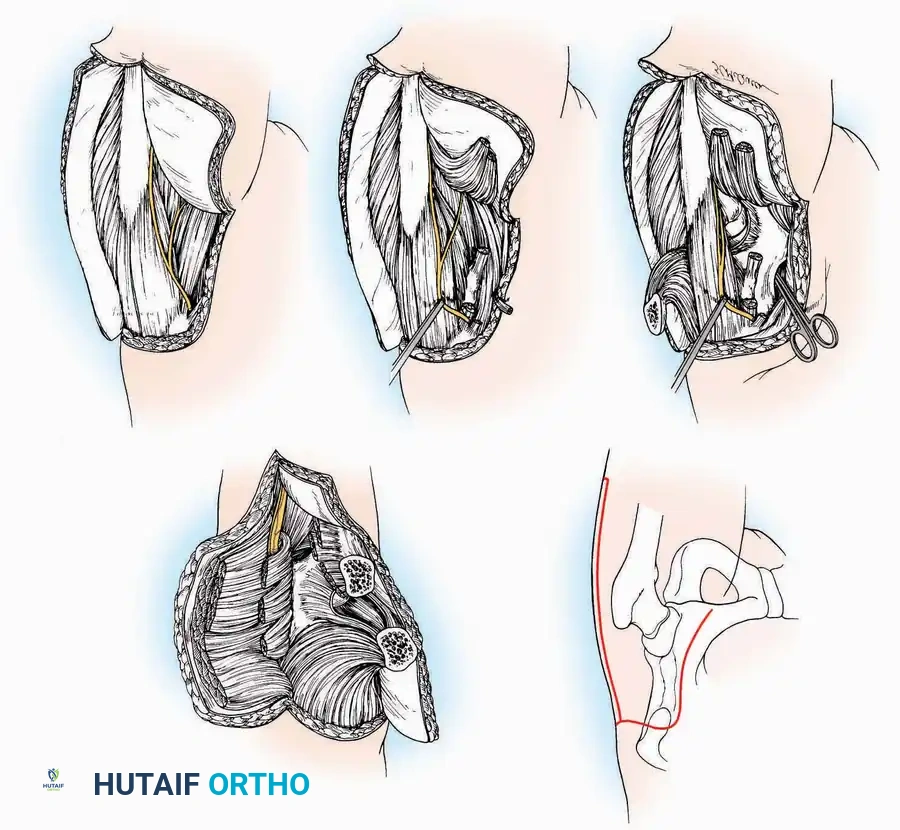

FUNDAMENTAL PRINCIPLES OF SURGICAL APPROACHES

In the evolution of operative orthopaedics, while many "new" surgical approaches have been described over the last several decades, few are truly original. The vast majority represent rediscovered historical exposures or nuanced modifications of established techniques. A master orthopaedic surgeon must possess an intimate understanding of cross-sectional and topographic anatomy to not only execute standard approaches but to dynamically adapt or design custom exposures when complex pathology dictates.

A meticulously planned surgical approach must provide unhindered access to all targeted osseous and soft-tissue structures. The incision must be of adequate length; a smaller incision that compromises visualization and makes the procedure exponentially more difficult can lead to catastrophic iatrogenic injury.

Soft Tissue and Incision Management

When practical, incisions should parallel or respect the natural resting skin tension lines (Langer’s lines) to optimize cosmesis and minimize hypertrophic scarring. For instance, a longitudinal incision crossing the flexor or extensor crease of a joint can precipitate a restrictive keloid, permanently impairing range of motion. Conversely, a longitudinal midlateral incision—particularly on the phalanges or the ulnar/fibular borders of the hand and foot—produces minimal scarring due to the relative immobility of the skin in these neutral axes.

Hemostasis and Tourniquet Application

A pneumatic tourniquet should be universally employed in extremity surgery unless specifically contraindicated (e.g., severe peripheral vascular disease, sickle cell trait, or compromised soft-tissue envelopes). The exsanguinated, dry field facilitates precise dissection, minimizes traumatic tissue handling, and significantly reduces operative time. Furthermore, a bloodless field is critical for the reliable identification and preservation of delicate cutaneous nerves, which often serve as anatomical landmarks for deeper internervous planes.

Even with temporary ischemia, an electrocautery unit must be utilized to meticulously coagulate small vessels crossing the incision, preventing postoperative hematoma formation upon tourniquet deflation. In axial or proximal regions where a tourniquet is unfeasible (e.g., shoulder, hip, pelvis), electrocautery becomes the primary modality for maintaining visualization and minimizing blood loss.